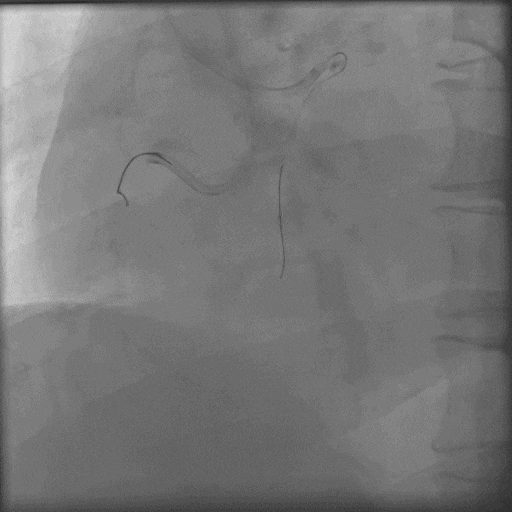

换用P200,导丝幸运进入血管真腔,

导丝通过后,Corsair微导管耐心旋转无法通过,小球囊无法通过;

采用M12、CP8-20导丝挤压(未留影),再小球囊掘进联合BAM技术;